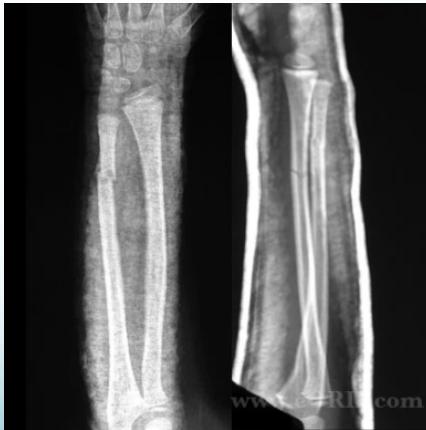

- Anatomical reduction is a must to preserve function

- More stable when fractures are not at same level

- 2 fractures at the same level = 100% unstable